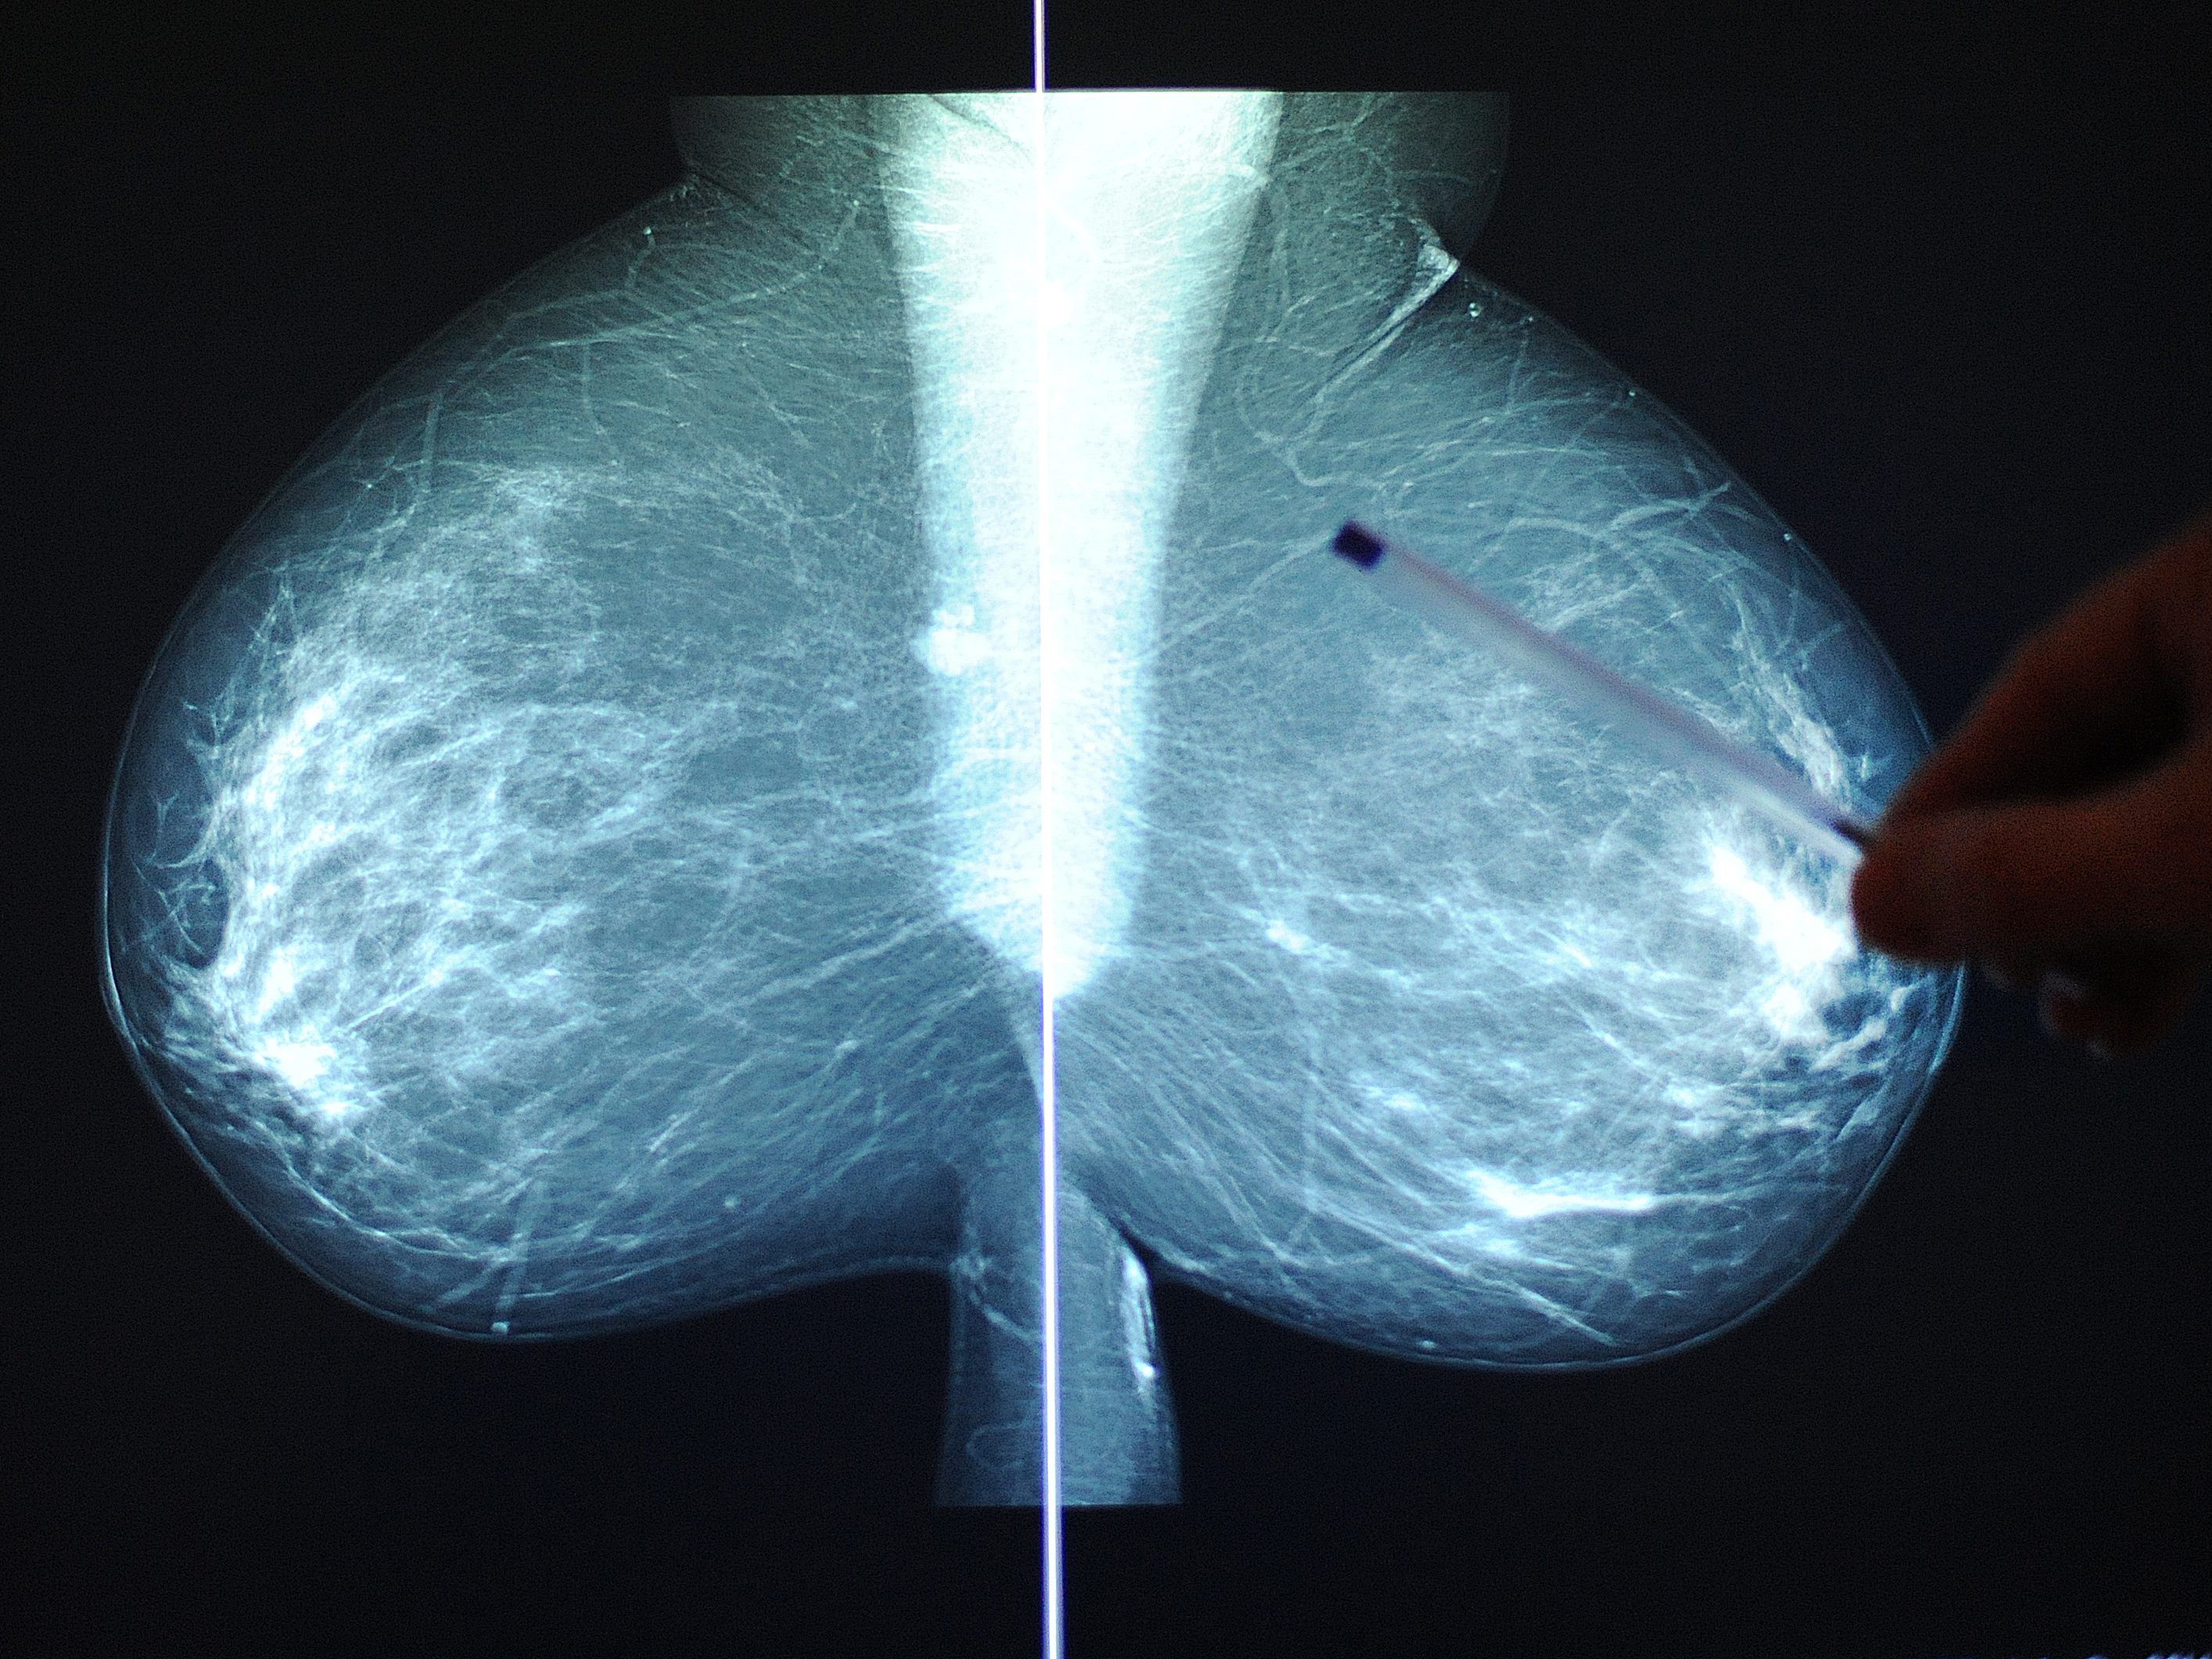

Studie: Nachtarbeit erhöht Krebsrisiko bei Frauen

Frauen, die nachts arbeiten, haben ein um 19 Prozent erhöhtes Krebsrisiko. Untersucht wurden Fälle von rund 1,3 Millionen Frauen weltweit, wobei besonders Frauen aus Europa und Nordamerika gefährdet sind. Ob die Nachtarbeit nun Ursache für Krebs ist, will die Studie nicht behaupten. So können auch Frauen mit Nachtberufen eher einen ungesunden Lebenstil pflegen oder etwa mehr rauchen.